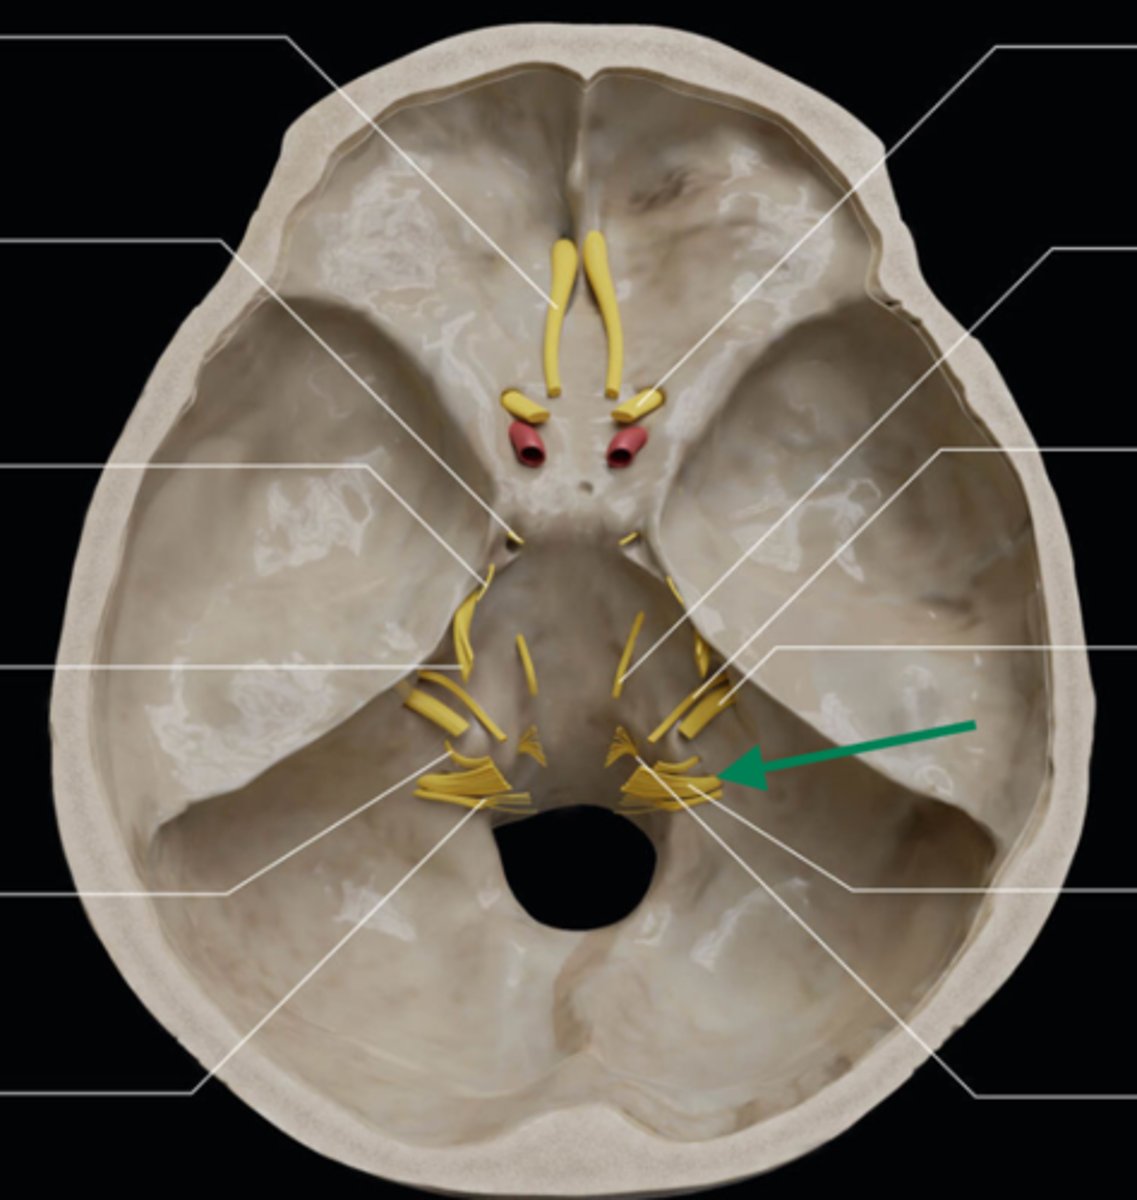

olfactory bulb

olfactory tract

optic nerve (CN II)

internal carotid artery

oculomotor nerve (CN III)

trochlear nerve (CN IV)

abducent nerve (CN VI)

trigeminal nerve (CN V)

facial nerve (CN VII)

vestibulocochlear nerve (CN VIII)

glossopharyngeal nerve (CN IX)

vagus nerve (CN X)

accessory nerve (CN XI)

hypoglossal nerve (CN XII)